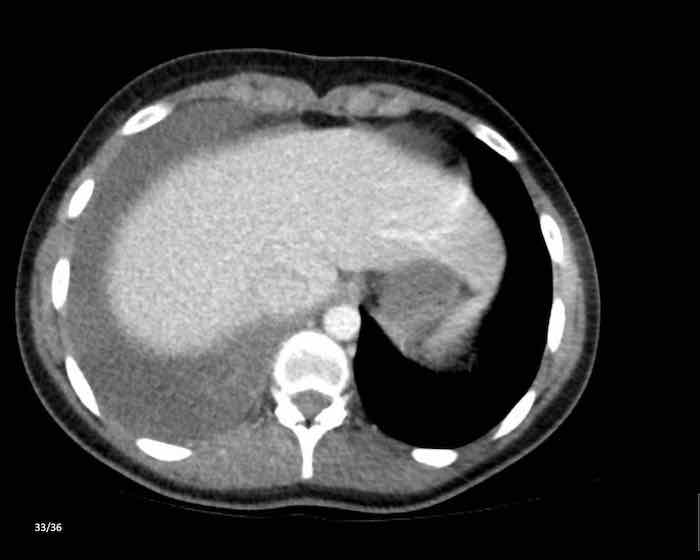

Các hình ảnh này của một phụ nữ 65 tuổi có tiền sử mắc bệnh Graves, một rối loạn tự miễn liên quan đến tình trạng cường chức năng tuyến giáp.

CT được thực hiện vì lý do ho ra máu.

Hình ảnh

Có một tuyến ức to lớn, cồng kềnh chứa mô mỡ đại thể.

Đây là hình ảnh điển hình của tăng sản tuyến ức.

Tăng sản tuyến ức trong bệnh Graves có liên quan đến tình trạng dư thừa hormone tuyến giáp và kháng thể kháng thụ thể thyrotropin.

Tình trạng này thường cải thiện sau khi điều trị thành công bệnh Graves.